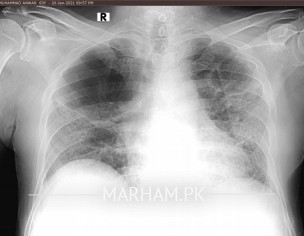

Dear doctors my father is in recovery phase after serious Covid19 today i have done x-ray and ECG of my father just for observe the recovery of inspiration systems re development because from last month he is still on 2ltr oxygen and staying at home with 96/97 sats rate.... Weakness ALHUMDULILLAH recover with good diet and MA SHA ALLAH clinically also very active now so plz doctor give expert opinion on it Medication vibramycine, osnate D, surbux z, loprain, steam 2/3 time in a day pouring and chest physio ongoing good oral intake. If any pulmonologist from rawalpindi Islamabad also pay attention i need your consultation. One x-ray is pervious 26Dec2020 dates mentioned plz review